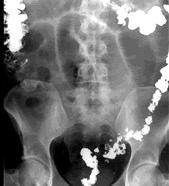

肠梗阻平片

肠梗阻腹部平片